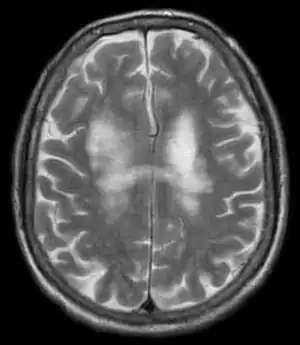

T2-weighted MRI showing progressive multifocal leukoencephalopathy

PML is diagnosed in a patient with a progressive course of the disease, finding JC virus DNA in spinal fluid together with consistent white-matter lesions on brain magnetic resonance imaging (MRI); alternatively, a brain biopsy is diagnostic[1] when the typical histopathology of demyelination, bizarre astrocytes, and enlarged oligodendroglial nuclei are present, coupled with techniques showing the presence of JC virus.[12]

Characteristic evidence of PML on brain CT scan images are multifocal, noncontrast enhancing hypodense lesions without mass effect, but MRI is far more sensitive than CT.[12] The most common area of involvement is the cortical white matter of frontal and parieto occipital lobes, but lesions may occur anywhere in the brain, such as the basal ganglia, external capsule, and posterior cranial fossa structures such as the brain stem and cerebellum.[12] Although typically multifocal, natalizumab-associated PML is often monofocal, predominantly in the frontal lobe.[12]